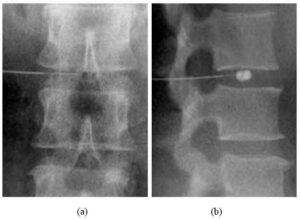

Mal di schiena, dolori cervicali, ernia del disco. Laddove non si ottengono risultati soddisfacenti interviene L'Ozonoterapia, che sempre piu' si...

Una singola iniezione di Ozono, un gas collegato con l'inquinamento atmosferico, potrebbe alleviare il dolore alla schiena che affligge milioni...